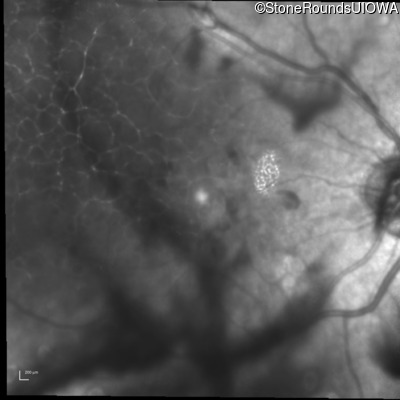

History

This 43 year old woman has experienced a gradual reduction in her central vision for the past 3 years.

Diagnosis & molecular findings

| Disease | Gene | Allele 1 variant(s) | Allele 2 variant(s) | Inheritance mode |

|---|---|---|---|---|

| Malattia Leventinese | EFEMP1 | Arg345Trp CGG>TGG | AD |